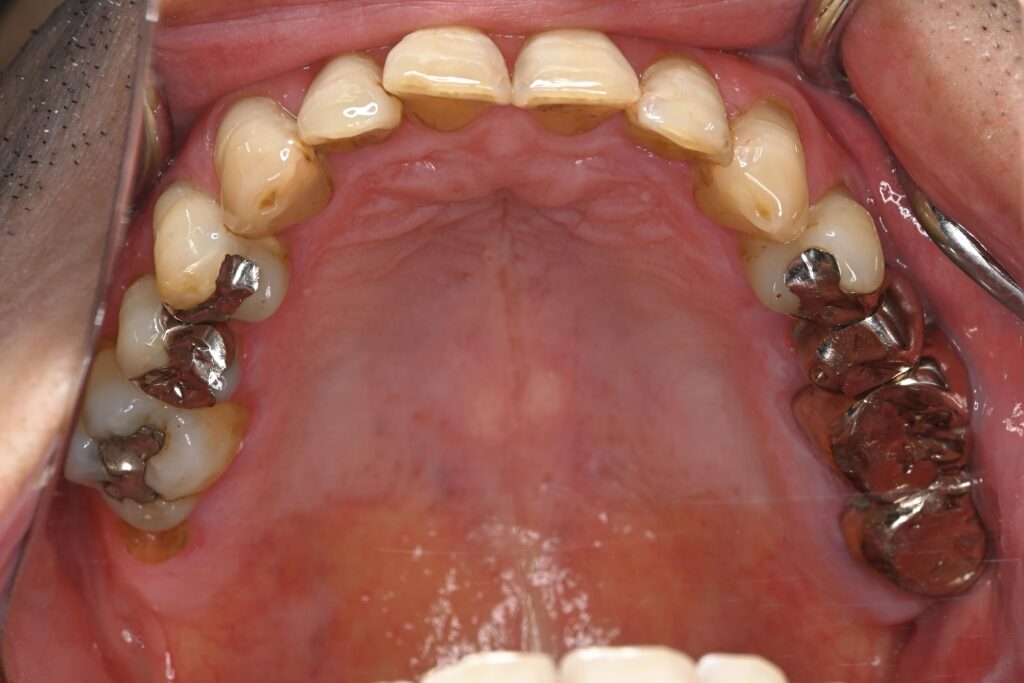

お口全体に虫歯や歯周病の原因となるプラーク(歯垢)が多く付着していました。右上奥歯は重度の虫歯で歯冠部(歯の頭)が失われており、左下奥歯は過去の治療箇所から細菌が入り込み、根の先に炎症が起きている状態でした。

患者様と相談の結果、期間や費用の面から矯正治療は行わず、「現在の噛み合わせを整えながら、金属をセラミックへやり替える治療」を選択しました。

セラミックを作製する前に全体的なトーンアップを行い、基準となる色を作りました。 - 審美修復(セラミック治療):

前歯の虫歯治療と、奥歯の古い金属をセラミックへ交換しました。 - 噛み合わせの調整:

切端咬合による噛み合わせの負担を考慮し、補綴材料としてジルコニアを選択しました。

ジルコニアは非常に高い強度と耐久性を持つ素材で、強い咬合力がかかる症例においても破折リスクを抑えやすい特性があります。 - 「色」へのこだわり: